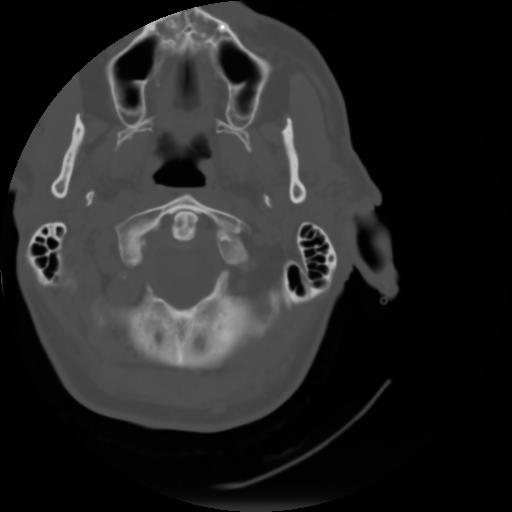

3 CEREBRO,,Axial,3.0,CEREBRO,,